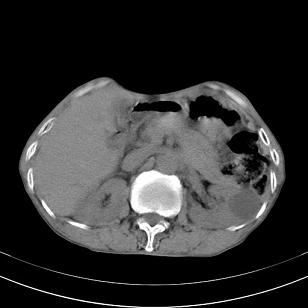

标题: 男,65岁,反复右上腹痛, [打印本页]

标题: 男,65岁,反复右上腹痛,

胃镜提示十二指肠占位